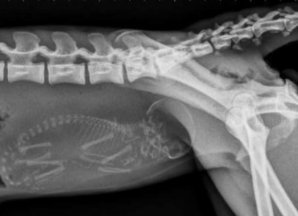

21 марта 1962 года состоялось первое испытательное, катапультирование на сверхзвуковой скорости. Американцы утверждают, что первым живым существом, испытавшим подобное, стал бурый медведь. Мишку выкинули на высоте более 10 километров и скорости почти 1400 км/час. Спустя 7 минут 49 секунд он благополучно приземлился. Кстати, выбор животного был довольно символичен во время "холодной" войны... Животные до сих пор являются частыми объектами для научных экспериментов. Их отправляли в космос, пришивали вторые головы, били током и клонировали. Большинство остались неизвестны, но многие получили значительную славу, правда, порой, посмертную, за помощь в совершении научных открытий, которые являлись настоящим прорывом для своего времени. Представляем вам животных-героев и первопроходцев, перевернувших современную науку.